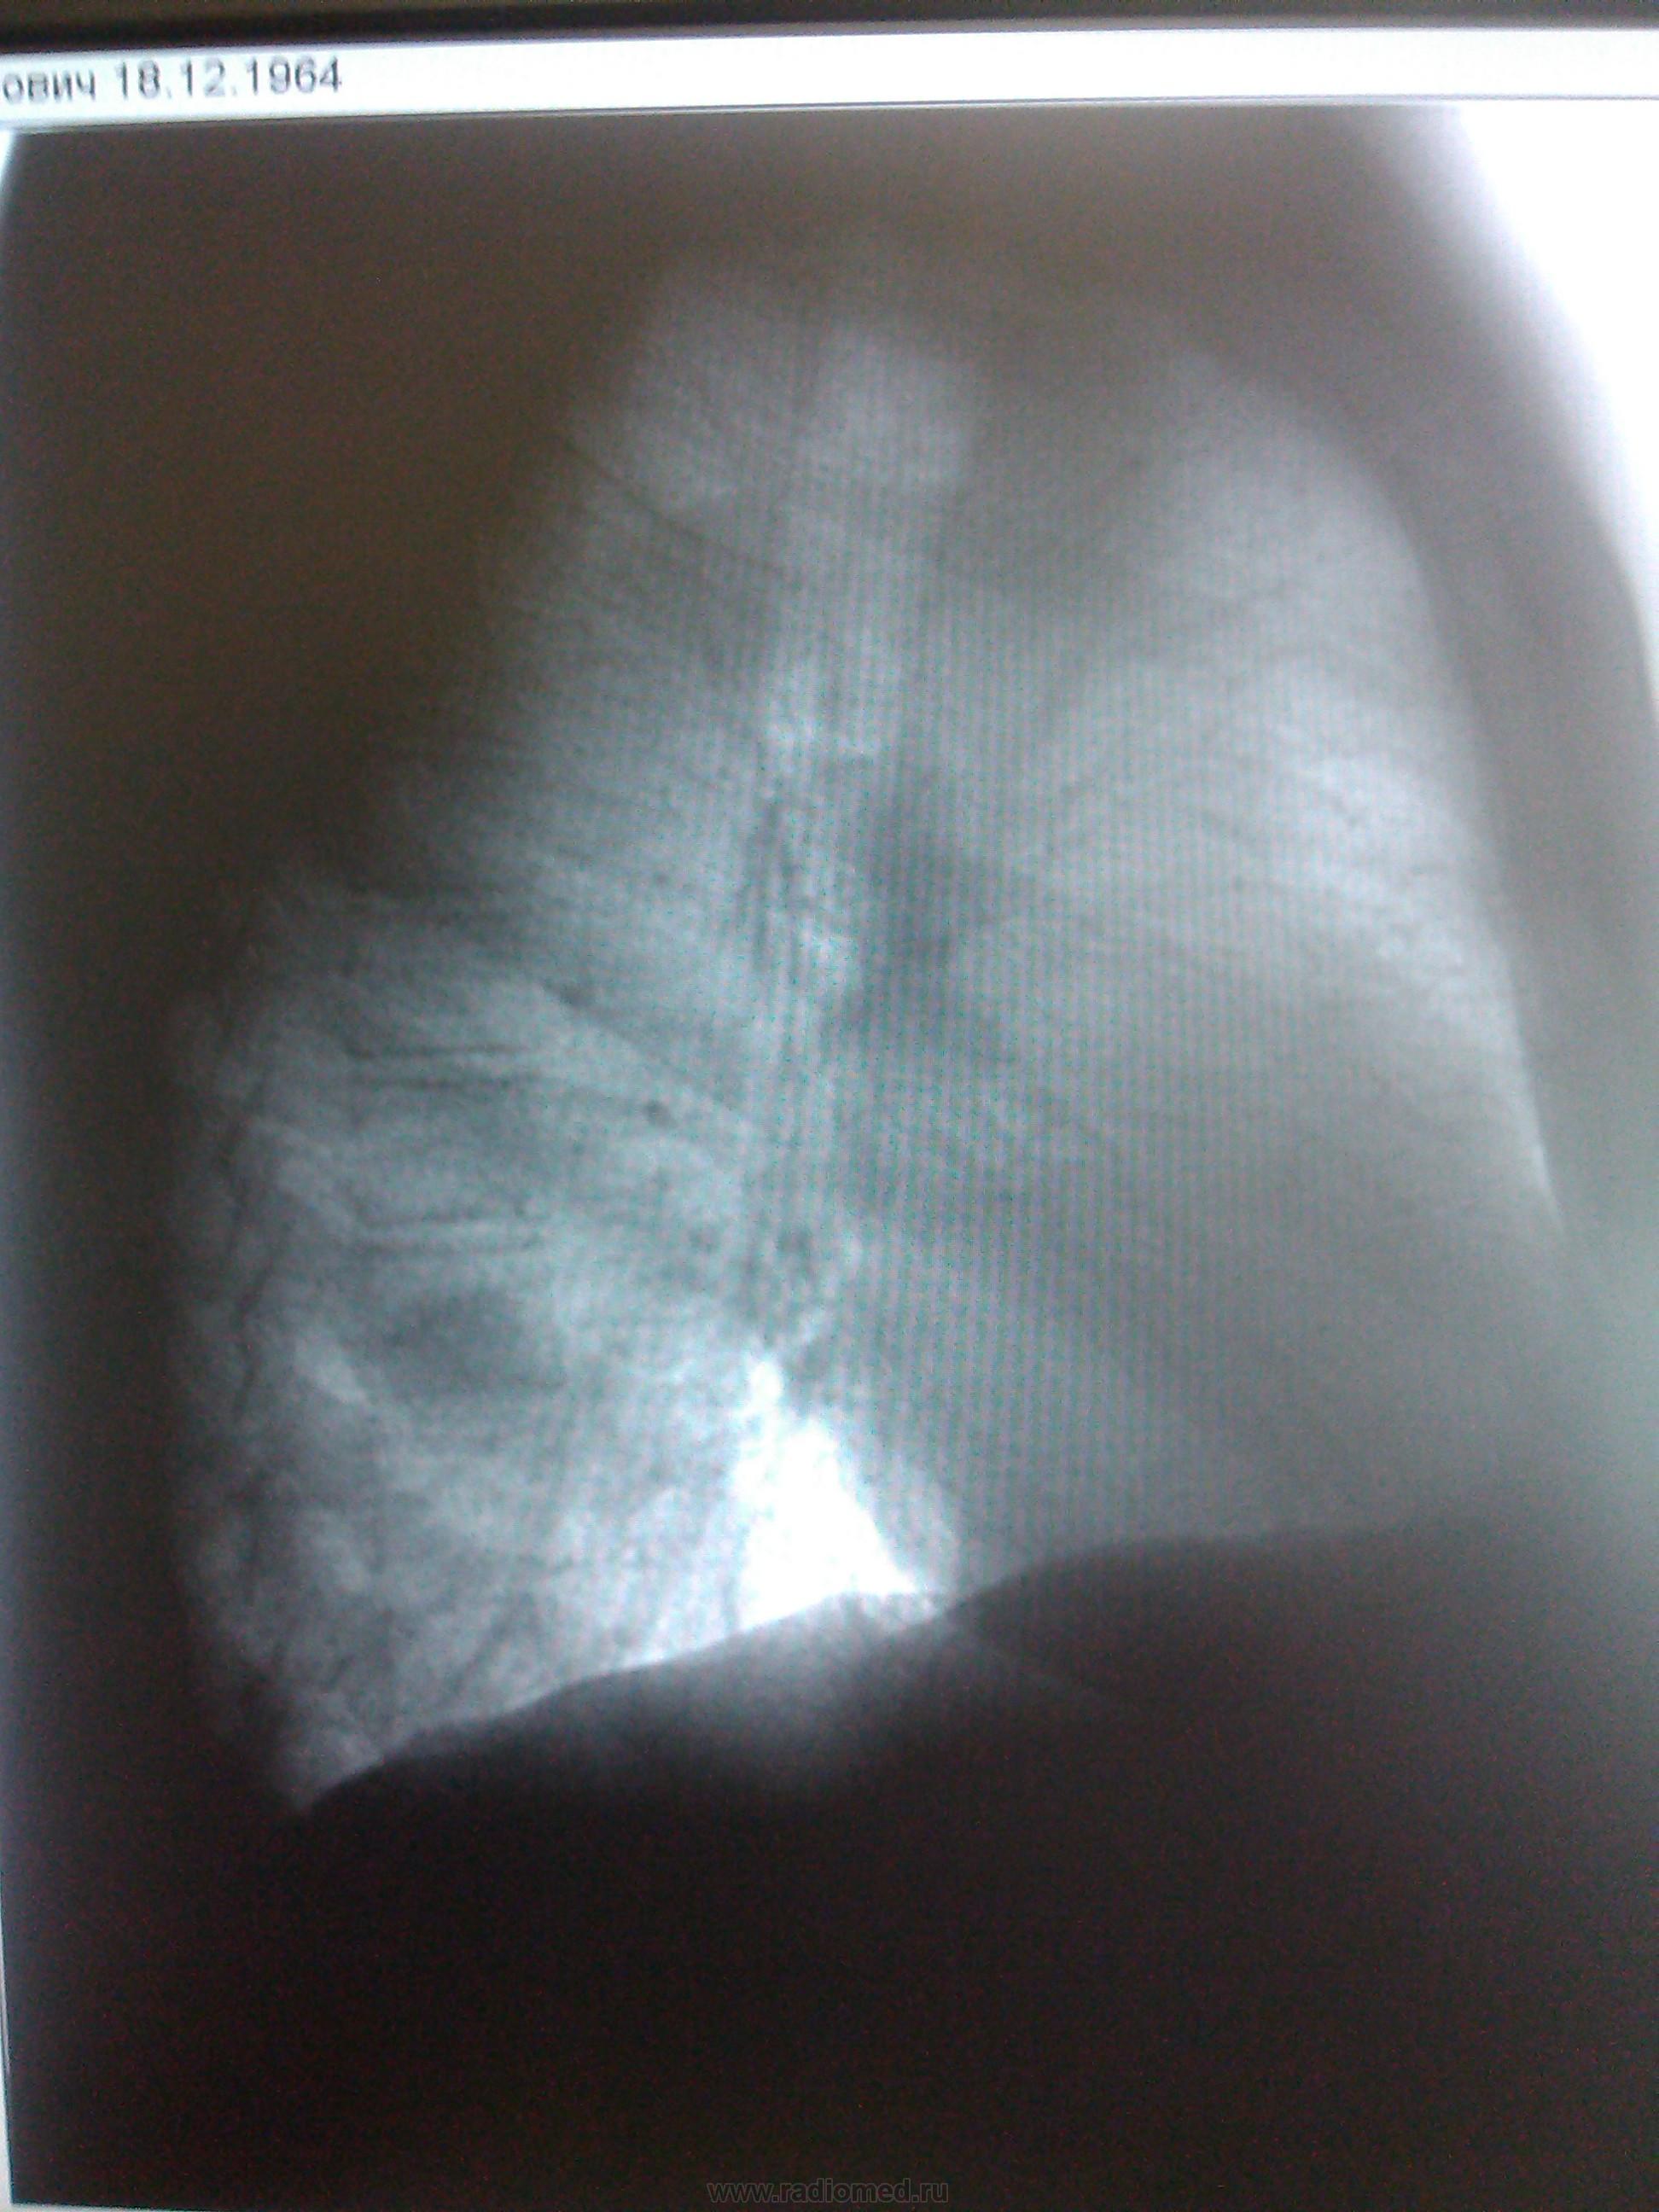

май 2014 г.

Пермферический рак нижней доли правого легкого в S9-10(учитывая отрицательную динамику за год)

позволяет заключить , что опухоль уже была.

Согласна с коллегами. Справа в S 10 периферическое образование, учитывая рост, более вероятно  C-r.  Cлева в среднем поле   воздушная киста

периферический рак справа + кисты в левом легком  в средних и нижних отделах